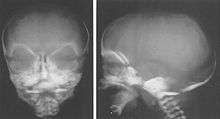

Children with Weaver syndrome tend to look similar and have distinctive physical and craniofacial characteristics, which may include several, but not all of the following features:

- Macrocephaly

- Large bifrontal diameter

- Flattened occiput

- Long philtrum

- Retrognathia

- Round face in infancy

- Prominent chin crease

- Large ears

- Strabismus

- Hypertelorism

- Epicanthal folds

- Downslanting palpebral fissures

Features distinguishing Weaver syndrome from Sotos syndrome include broad forehead and face, ocular hypertelorism, prominent wide philtrum, micrognathia, deep-set nails, retrognathia with a prominent chin crease, increased prenatal growth, and a carpal bone age that is greatly advanced compared to metacarpal and phalangeal bone age.[10]